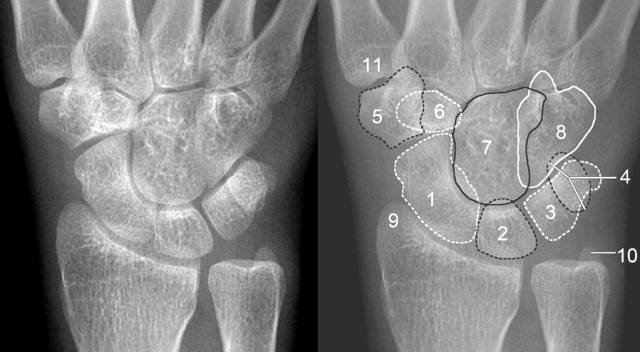

1、腕关节X线下的正常形态

( 1)正位片上:前后排腕骨后缘形成光滑的弧线;前后排腕骨不重叠;头、钩、月、三角骨间形成十字间隙。月骨于正位片上为楔形、侧位片上为月牙形,窝状关节面朝前、且与头状骨紧贴。

1.舟骨 2.月骨 3.三角骨 4.豆状骨 5.大多角骨 6.小多角骨 7.头状骨 8.钩骨 9.桡骨茎突 10.尺骨茎突 11.第一掌骨基部

(2)侧位片上:桡骨纵轴通过月骨和头骨;前排腕骨自下而上分别为大、小、头、钩骨,后排自下而上为舟、月(豆)、三角骨。